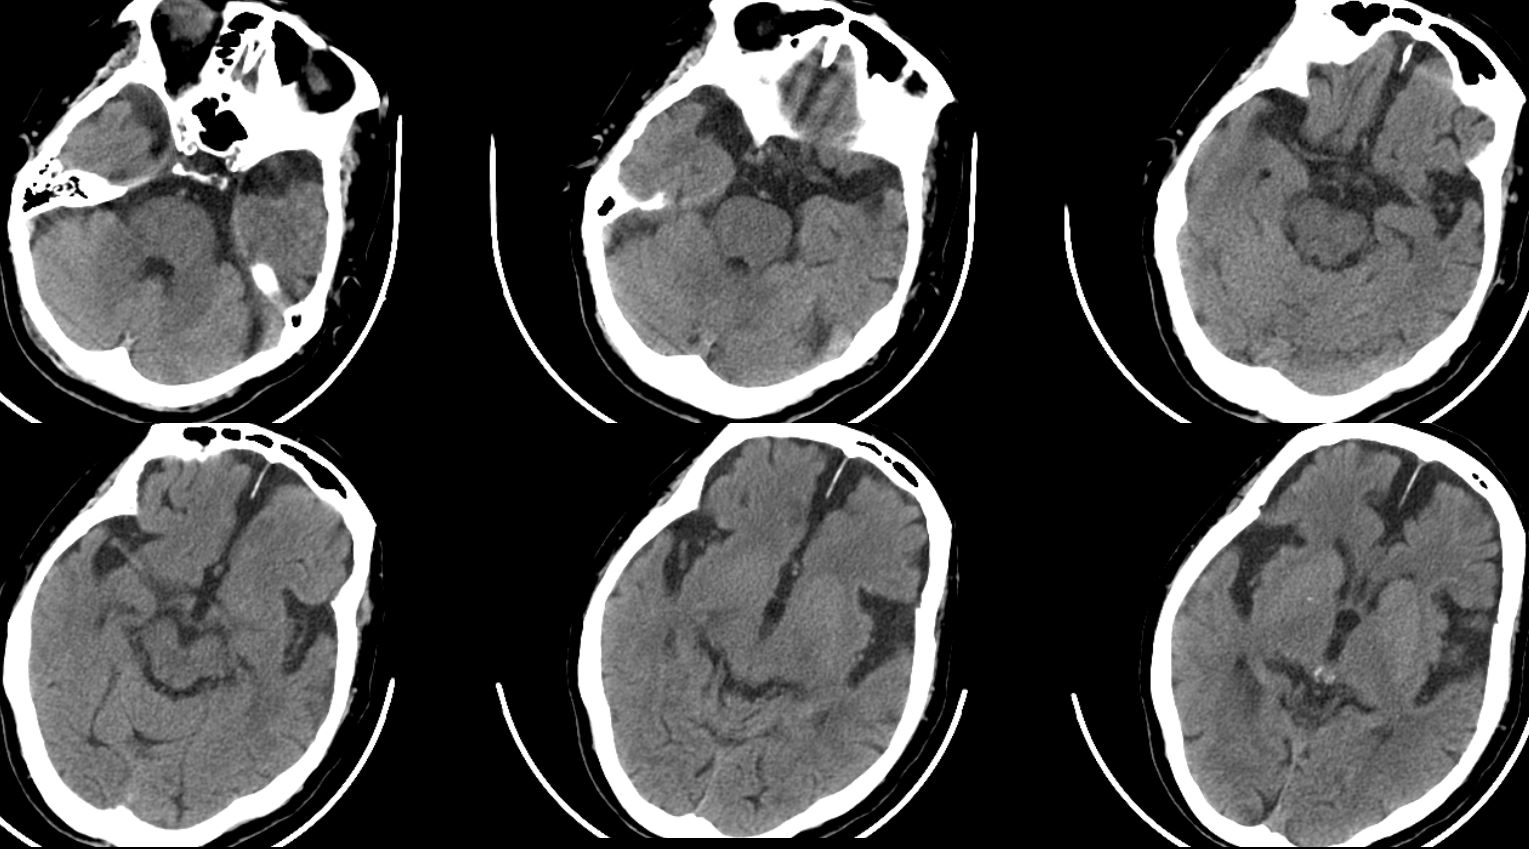

患者老年女性,83岁,中午午饭后休息时突发吐词不清伴右侧肢体乏力于晚上7电左右来院。发病后已7小时,超时间窗,故未予溶栓。既往有“高血压病”病史多年,血压控制情况不详。查体:神志嗜睡,GCS评分=E3V4M6=13分,右上肢肌力1-2级,右侧肌力1级,右侧巴氏征阳性。NHISS评分:嗜睡1、构音2、面瘫1、右侧上下肢4+4=12分;急诊头颅及颈部血管CTA :左侧大脑中动脉部分未见显影,其周围可见多发小血管影。急诊头颅平扫提示:双侧额、颞部硬膜下积液;脑白质疏松;脑萎缩。

评估后有手术指征,急诊行血管内治疗,术前评估患者考虑局部狭窄合并急性栓塞可能性大。